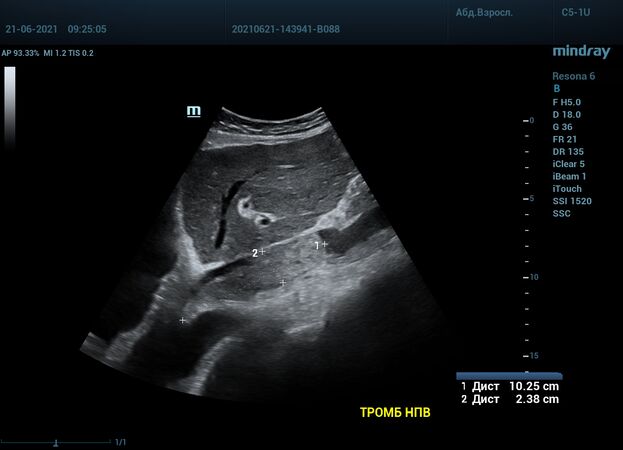

Интересный случай из практики нашего врача-аппликатора. Использовался экспертный ультразвуковой прибор Mindray Resona 6, стандартные заводские пресеты и автоматическая оптимизация iTouch. В эхокардиографии всегда помогает колорайзинг, чаще всего используется оранжевый оттенок. Пациент обследуется перед оперативным лечением по поводу онкологии почки. Вены нижних конечностей у данного пациента без особенностей, сжимаемы и проходимы. Казалось бы, проблема тромбоза миновала но в процессе эхокардиографического исследования, при сканировании нижней полой вены в субкостальном сечении, определяется эхогенное образование. Образование на месте просвета нижней полой вены. Вена расширена, эхогенное включение проникает в правое предсердие. По краю тромба в цветопотоковой визуализации определяется кровоток. Онкологическое заболевание почки осложнилось тромбозом почечной вены, с распространением тромба в нижнюю полую вену и правое предсердие. Изюминку добавляет то, что в других эхокардиографических сечениях тромб совершенно не виден.